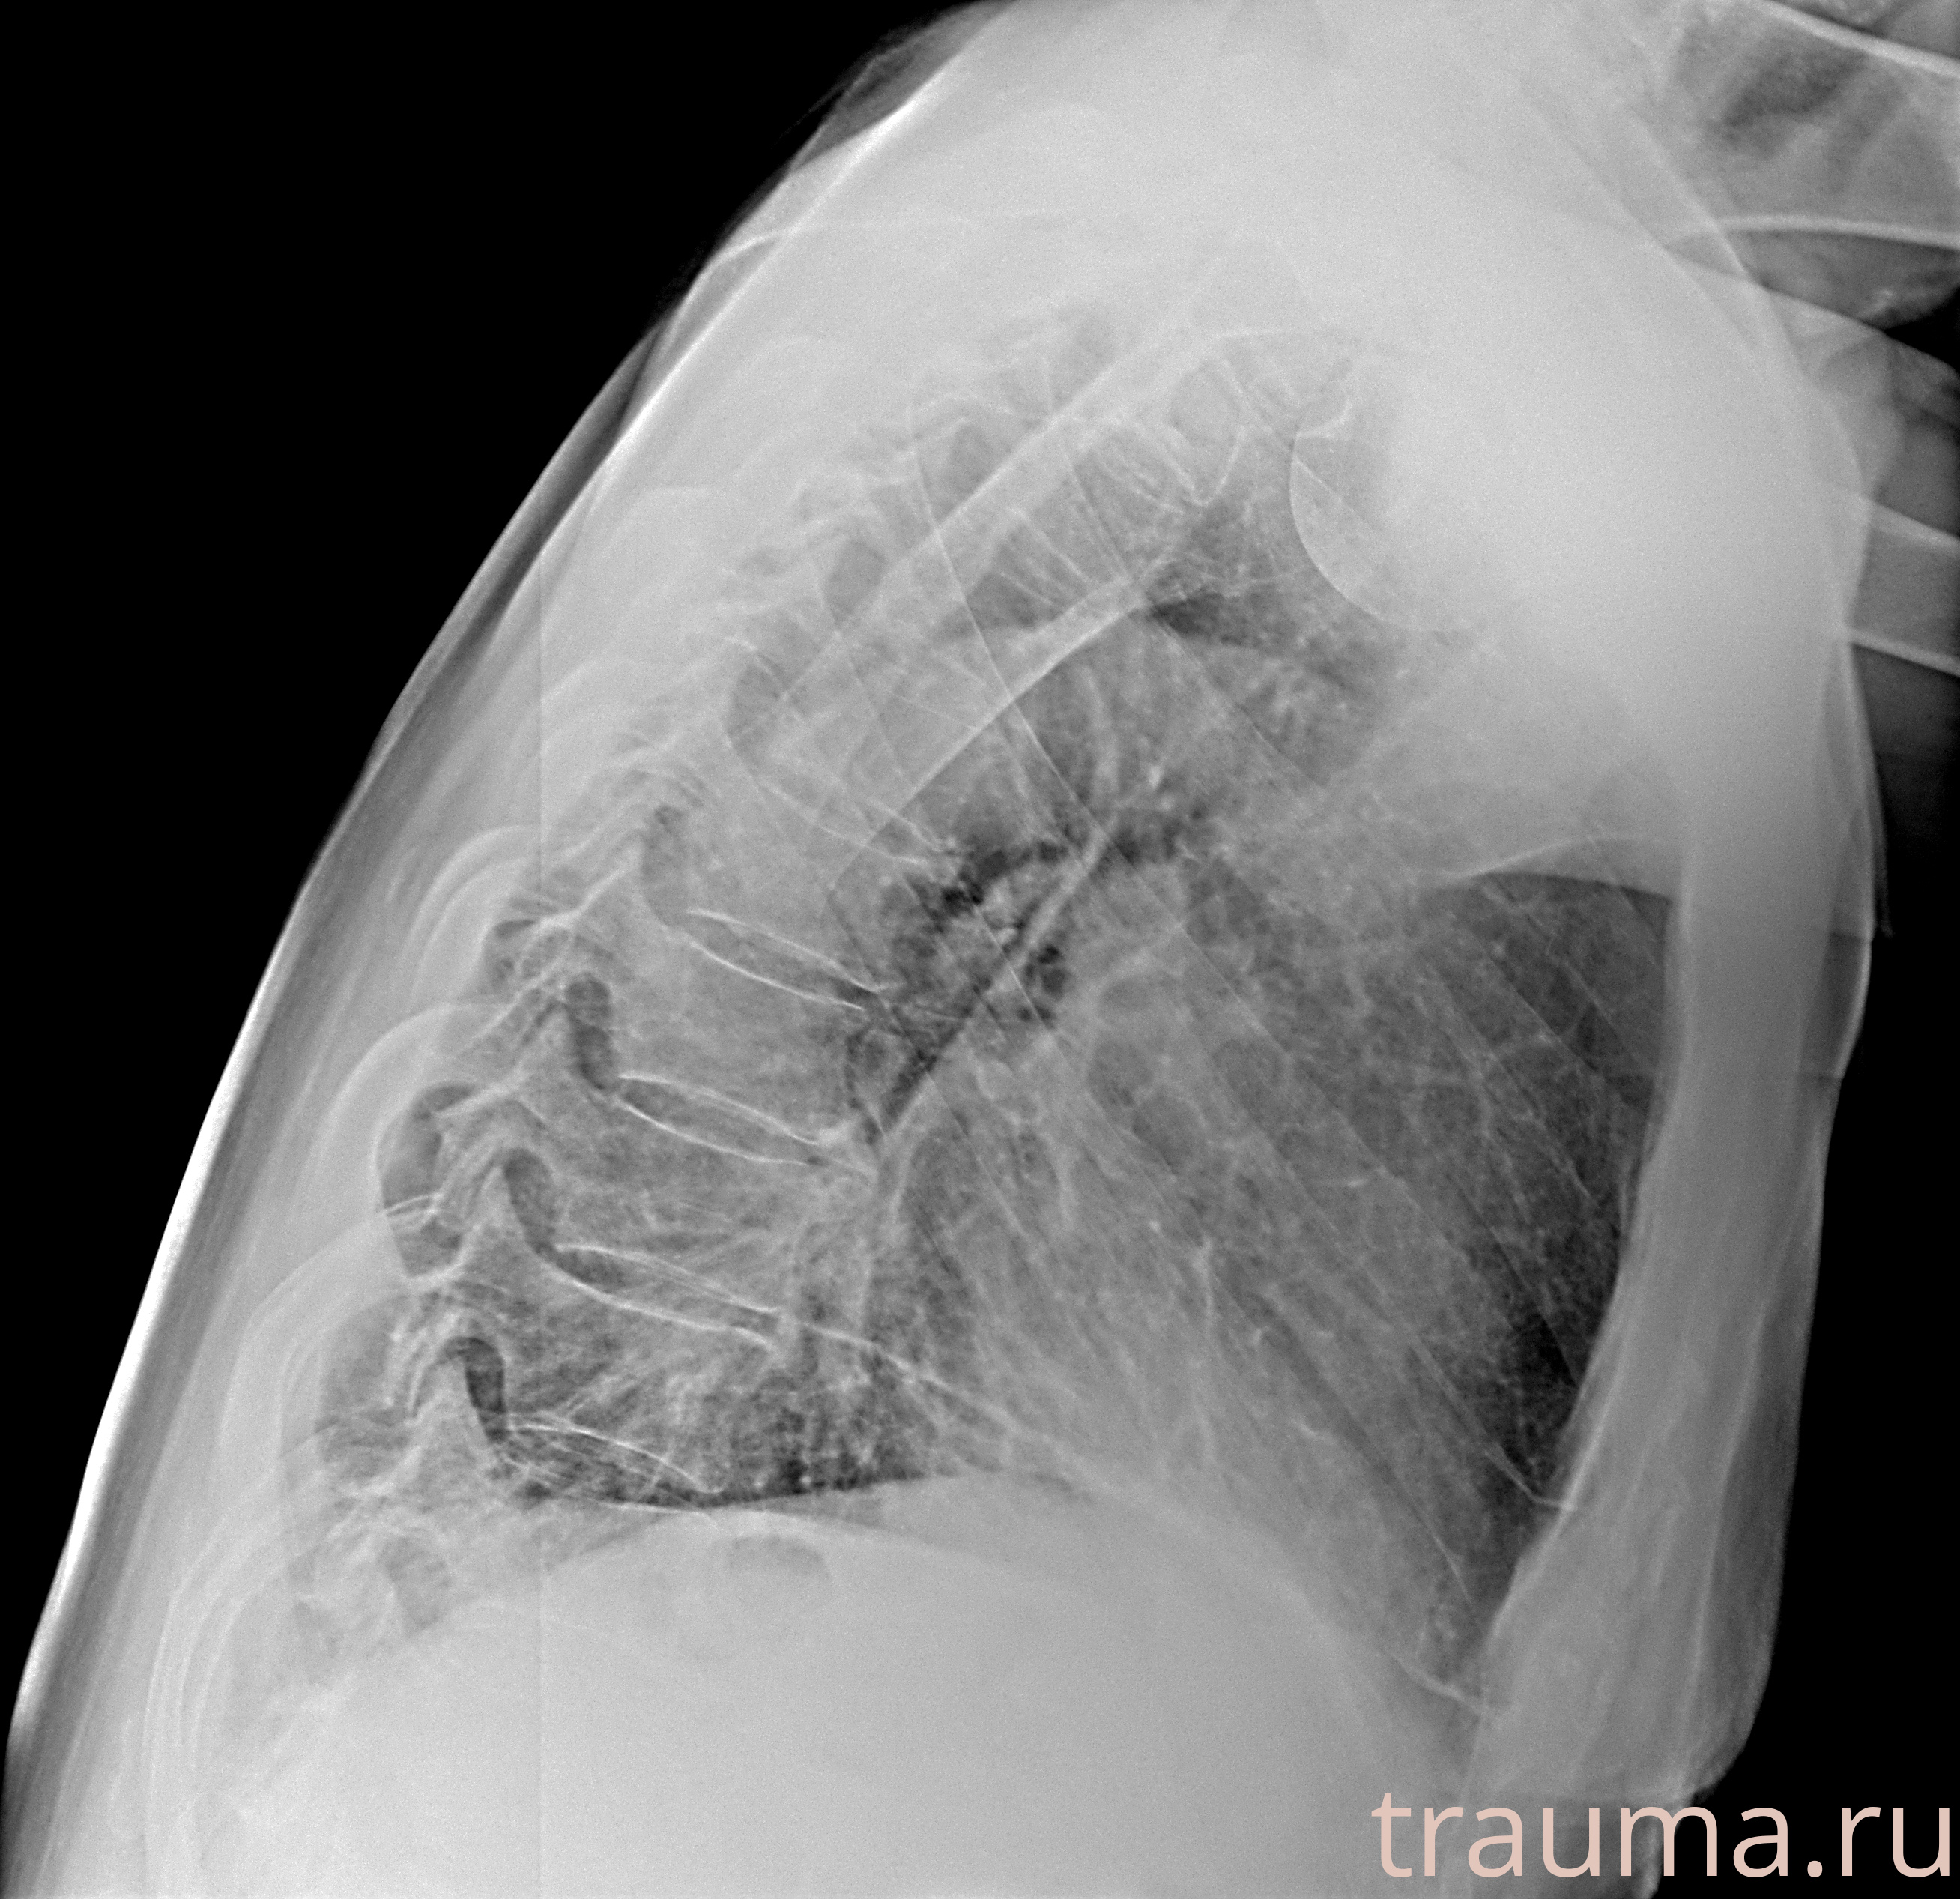

Рентген на дому: по вашему адресу приезжает врач-рентгенолог, травматолог-ортопед с мобильным рентгеновским аппаратом, проводит диагностику травмы или заболевания, делает необходимые рентгенограммы, дает рекомендации по дальнейшему лечению. Получить качественные снимки в домашних условиях возможно благодаря уникальной методике, разработанной МосРентген Центром для института  Склифосовского